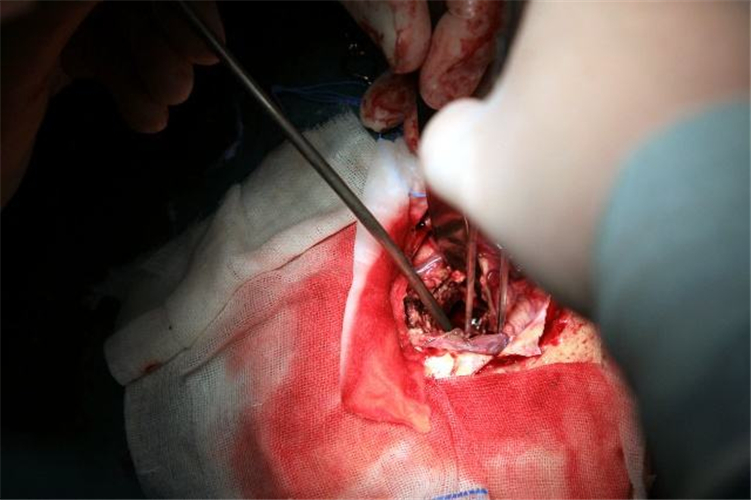

手術治療腦血管痙攣

手術治療腦血管痙攣的

手術治療腦血管痙攣合併動脈瘤

腦血管痙攣手術中